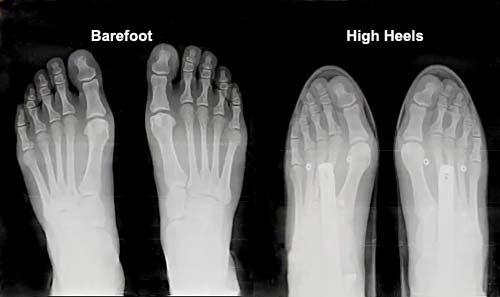

First, please take a second to really look at the bones in the picture above and below. I’ll meet you on the other side.

– compression of foot bones

🦶 Choose heels with a rounded toe box instead of pointy toes (which compress your foot bones even more).